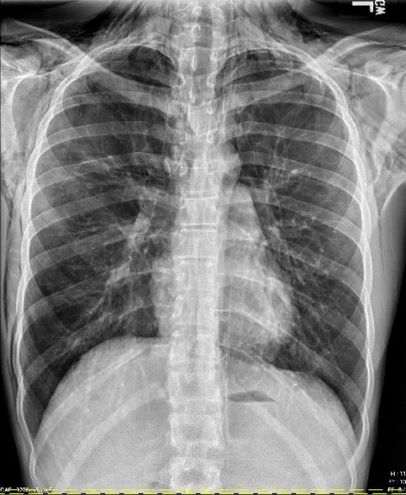

Initial Chest X-ray

Findings: There is extensive pneumomediastinum with air dissecting along the esophagus, mediastinum, and supraclavicular soft tissues, along the lateral chest wall bilaterally, greater on the right.

No definite pneumothorax is visualized.

There is no focal consolidation. There is no pleural effusion. The heart size is normal. The bones are unremarkable.

Impression: Marked pneumomediastinum with air dissecting across the soft tissue planes.

Anterior-Posterior (AP) and Lateral Chest X-ray